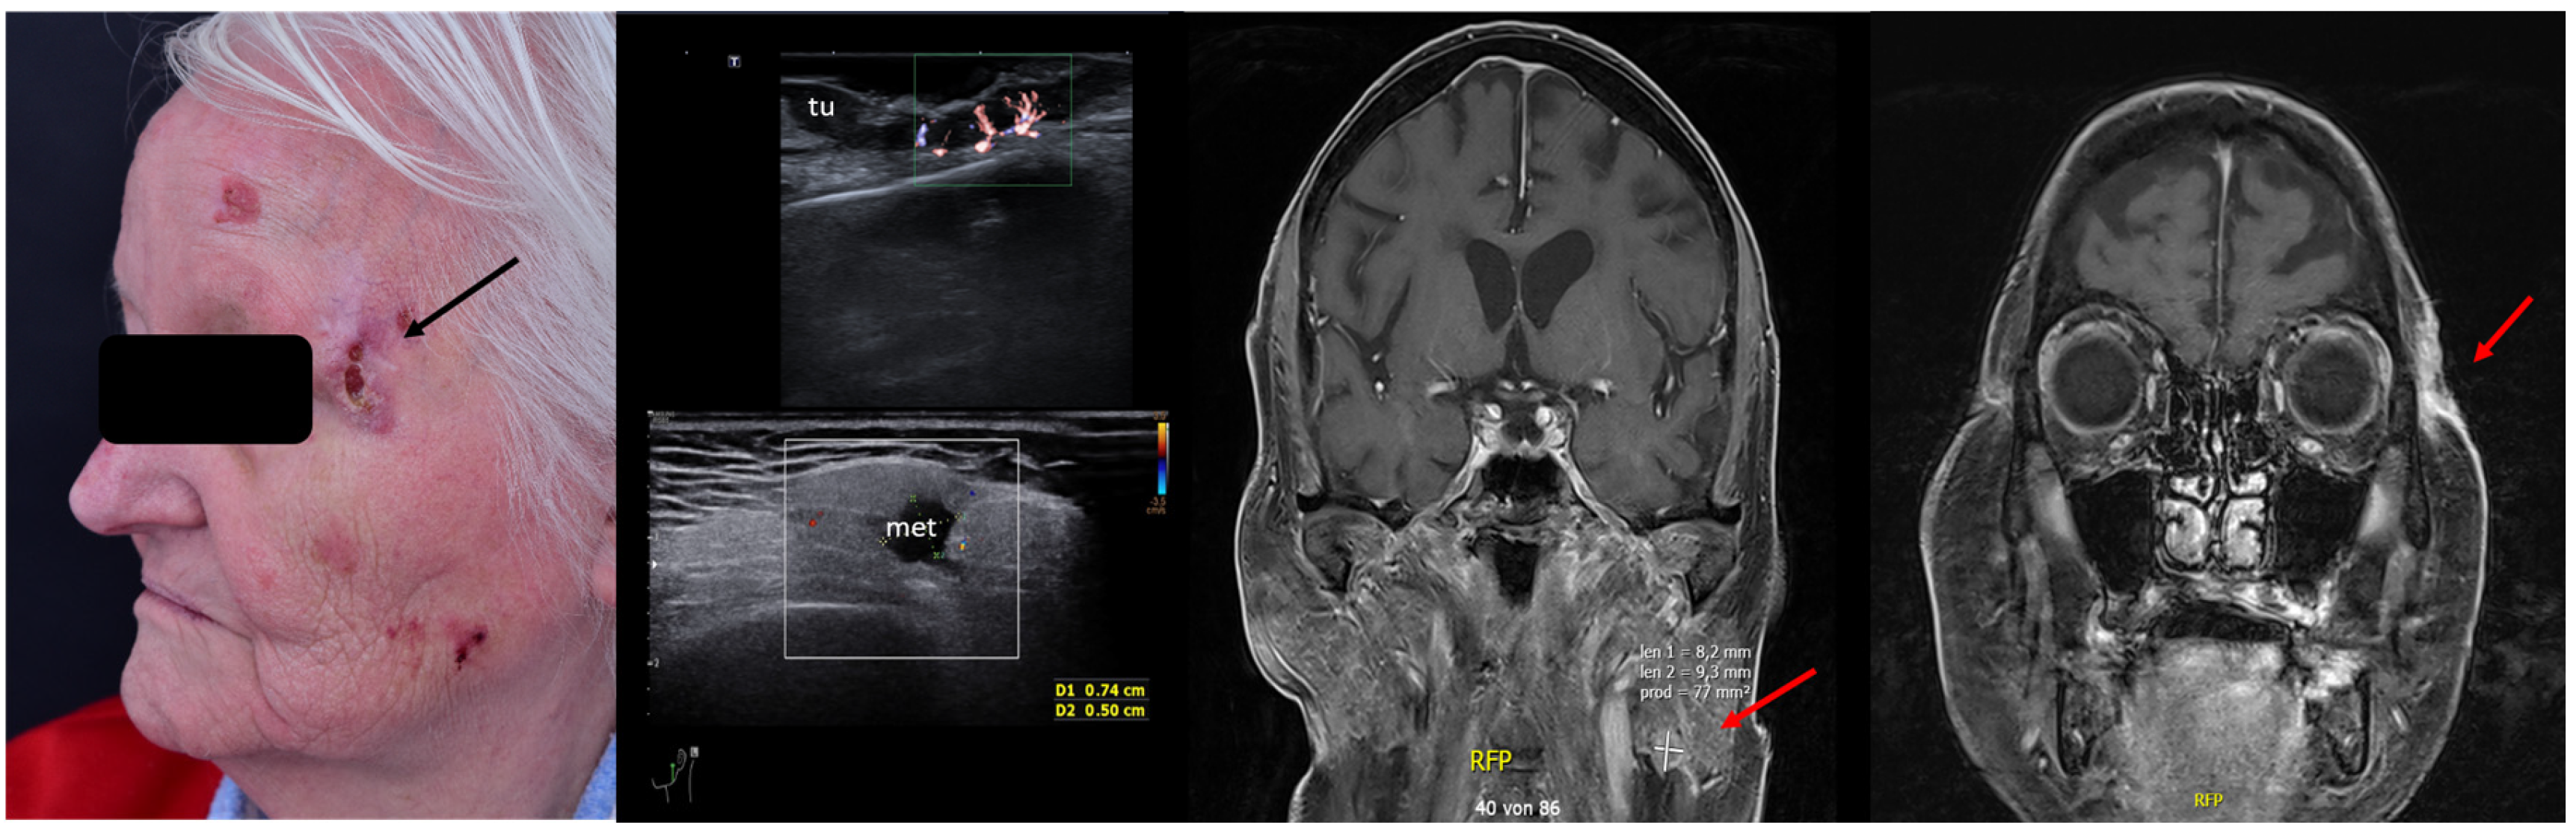

2. Enhancement of Diagnostic Accuracy, Avoidance of Misdiagnosis, Early Identification of Local Relapse

10. Avoidance of Unnecessary Surgeries due to Patient Up-Staging

- Catalano, O.; Crisan, D.; Díaz, C.P.G.; Cavallieri, F.; Varelli, C.; Wortsman, X. Ultrasound Assessment of Skin Tumors Local Recurrence. J. Ultrasound Med. 2023, 42, 2439–2446. [Google Scholar] [CrossRef]